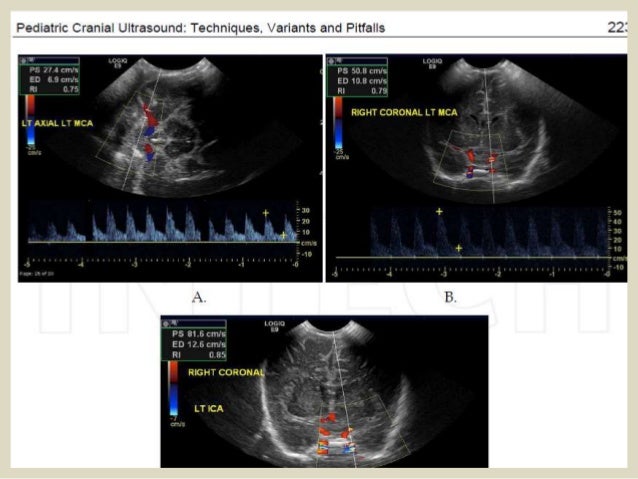

59. 59. Acute ischemia: Evaluation of diffuse brain edema is technically challenging on neurosonography. As the size of the ventricles varies considerably, ventricular size is unreliable as a parameter in assessing the mass effect. The usual observation in the cases of ischemia is a combination of diffuse increase in the echogenicity of ganglionic areas with associated obliteration of cisterns and small capacity of the ventricles. CT and/or magnetic resonance imaging (MRI) still remain as superior techniques in assessing diffuse intracranial ischemia Serial Doppler examination of the intracranial vessels and circle of Willis is helpful in evaluating the severity of intracranial ischemia. Diastolic flow, reflected in Resistive Index (RI) is a measure that will indicate the hemodynamic status of intracranial flow. Coronal USG at two levels demonstrating the subtle increase in the cerebral parenchymal echoes in a patient with acute ischemia (secondary to meconium aspiration). Note the small-capacity ventricles and obliterated cisternal spaces

60. 60. Cerebral edema. Increased parenchyma echogenicity. Decreased sulcal/gyral differentiation. Decrease vascular pulsations.